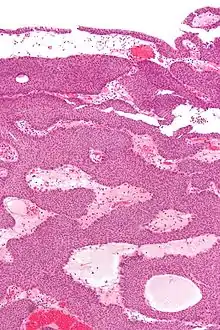

| Micrograph of an inverted papilloma of the urinary bladder. H&E stain. | |

Histopathology representing an inverted papilloma of the urinary bladder that was cystoscopically resected. Hematoxylin and eosion stain.